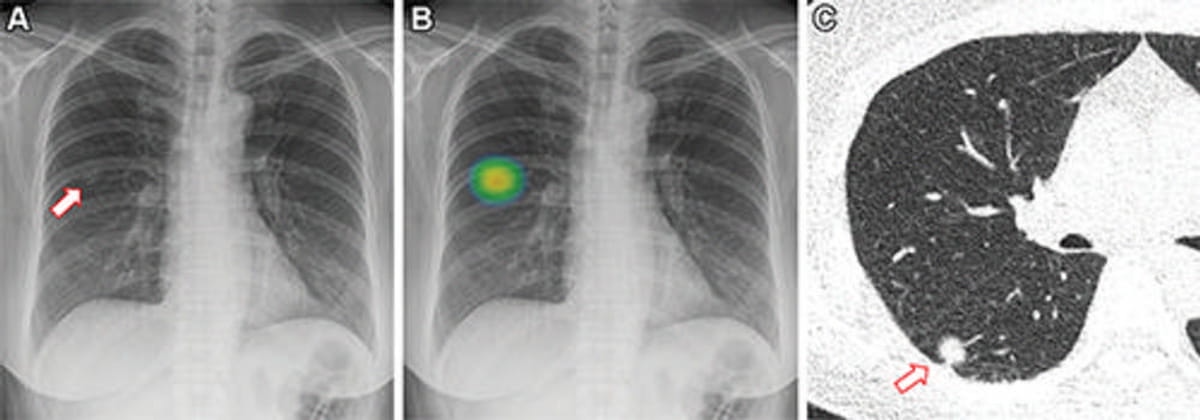

Artificial intelligence (AI) assessments of chest X-rays identified 28 percent of a 17,000 plus cohort of never-smokers as being at high-risk for lung cancer, according to research to be presented at the annual Radiological Society of North America (RSNA) conference next week.